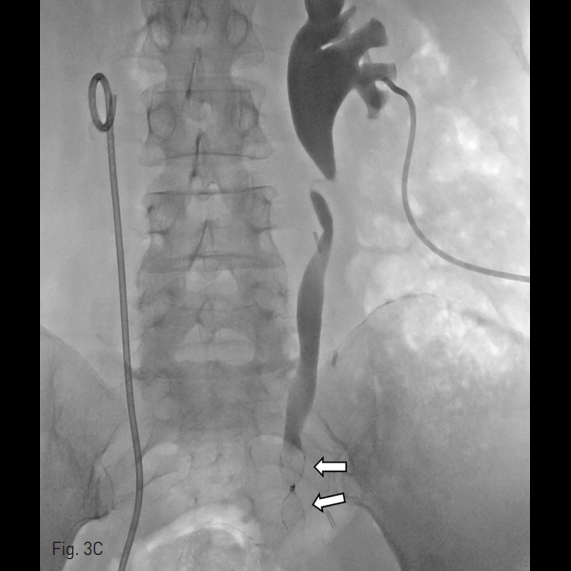

경피적 신루 도관 (percutaneous nephrostomy tube)을 통해 시행한 우측 순방향 요관조영술에서 우측 요관의 원위부에서의 조영제 누출이 확인되었다 (Fig. 1).

Fig. 1

Right antegrade ureterogram through the PCN tube shows contrast medium leakage (arrows) from the distal tip (arrowhead) of the right ureter.